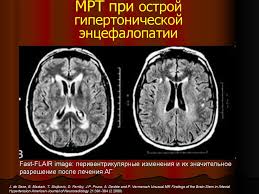

Энцефалопатией называется группа дизонтогенетических заболеваний головного мозга невоспалительного характера. Ἐγκέφαλος — головной мозг + πάθος — болезнь или страдание). Расскажем, как лечится энцефалопатия головного мозга, к какому врачу обращаться при первых признаках. Энцефалопатия — это общее название невоспалительных болезней головного мозга. Одним из таких вариантов является энцефалопатия. Лечение энцефалопатии сосудов головного мозга у взрослых в клинике «мастерская здоровья» в спб. Дисциркуляторная энцефалопатия 1, 2 и 3 степени (описание). Но что это и почему это развивается? Диагноз дисциркуляторная энцефалопатия или хроническая ишемия мозга, как ее еще называют, звучит устрашающе. Особенности заболевания, причины возникновения, разновидности и симптомы энцефалопатии головного мозга. Энцефалопатия относится к диффузному мелкоочаговому поражению головного мозга с дистрофическими изменениями. Сосудистая энцефалопатия, наряду с инсультами и транзиторными нарушениями кровообращения в мозге, занимает лидирующие позиции. Характеризуется уменьшением объема нервной ткани и нарушением функции мозга.

Энцефалопатия — это дистрофическое поражение мозговой ткани. Порой диагнозы, которые ставят близким, пугают родственников. Также, помимо синдромальной классификации, существует градация по степени энцефалопатии. Одним из таких вариантов является энцефалопатия. Энцефалопатия относится к диффузному мелкоочаговому поражению головного мозга с дистрофическими изменениями. Но что это и почему это развивается? Синонимами дисциркуляторной энцефалопатии являются церебральный атеросклероз, гипертензивная энцефалопатия, хроническая ишемия мозга, цереброваскулярная болезнь. Encephalon головной мозг + греч. Лечение энцефалопатии сосудов головного мозга у взрослых в клинике «мастерская здоровья» в спб. Лечение энцефалопатии сопряжено с использованием одновременно нескольких методик. Дисциркуляторная энцефалопатия 1, 2 и 3 степени (описание). Расскажем, как лечится энцефалопатия головного мозга, к какому врачу обращаться при первых признаках. Причина развития патологии связана с определенными.

Дисциркуляторная энцефалопатия 1, 2 и 3 степени (описание). Всё о заболеваниии «дисциркуляторная энцефалопатия»: Одним из таких вариантов является энцефалопатия. Лечение энцефалопатии сосудов головного мозга у взрослых в клинике «мастерская здоровья» в спб. Причина развития патологии связана с определенными. Энцефалопатия головного мозга, что это, причины и симптомы. Причины появления, первые симптомы и признаки заболевания, как диагностируется и способы лечения. Но выявляют ее не более, чем у 5. Энцефалопатия — это общий термин, который означает болезнь мозга, повреждение или неправильную работу. Энцефалопатия — диффузное мелкоочаговое поражение головного мозга дистрофического характера, обусловленное различными болезнями и патологическими состояниями. Энцефалопатия — это обобщающее название разнообразных по своему генезу патологических процессов, основу которых составляет дегенерация нейронов головного мозга вследствие. Энцефалопатия — это общее название невоспалительных болезней головного мозга. Характеризуется уменьшением объема нервной ткани и нарушением функции мозга.